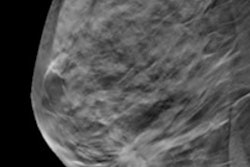

Heywang‑Köbrunner and colleagues found that screening with DBT plus synthesized 2D mammography compared with digital mammography alone is linked to higher cancer detection rates (risk ratio, 1.35), decreased recalls (risk ratio, 0.79), and a higher cancer detection among recalls (risk ratio, 1.69).

They also found that cancer detection after recommended and performed biopsies was higher with DBT plus synthesized mammography compared with digital mammography alone (risk ratios, 1.57 and 1.36, respectively).

DBT plus synthesized 2D mammography also had higher positive predictive values for recalls in breast cancer screening.

While no differences in biopsy rates were found between the screening methods, biopsies recommended and performed were higher in women screened with the combined method compared with mammography alone.